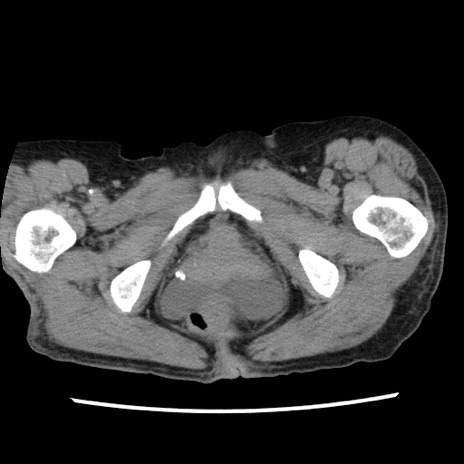

症例1(横断像)

【症例】80歳代女性

【主訴】腹痛

【現病歴】8時間前から腹痛あり来院。

【既往歴】糖尿病、脂質異常症、子宮体癌にて子宮全摘術

【身体所見】意識清明・会話良好だが腹痛で苦悶様、全腹部にわたって反跳痛と圧痛あり

【データ】WBC 13600、CRP 0.14、LDH 224、CK 90